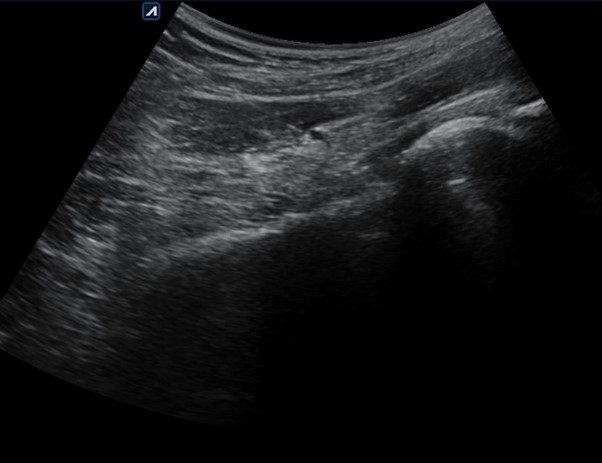

특히 주사치료의 경우,

이상근의 정확한 위치를 파악하는 것이 핵심입니다.

초음파를 이용해서 실시간으로 근육의 상태를 확인하면서

정확한 부위에 약물을 주입하는 것이 중요하죠.

그림4.png

그림5.jpg 촬영 일시: 2025.03.29

<Fig 2. 원인 부위에 SI 치료하는 영상>